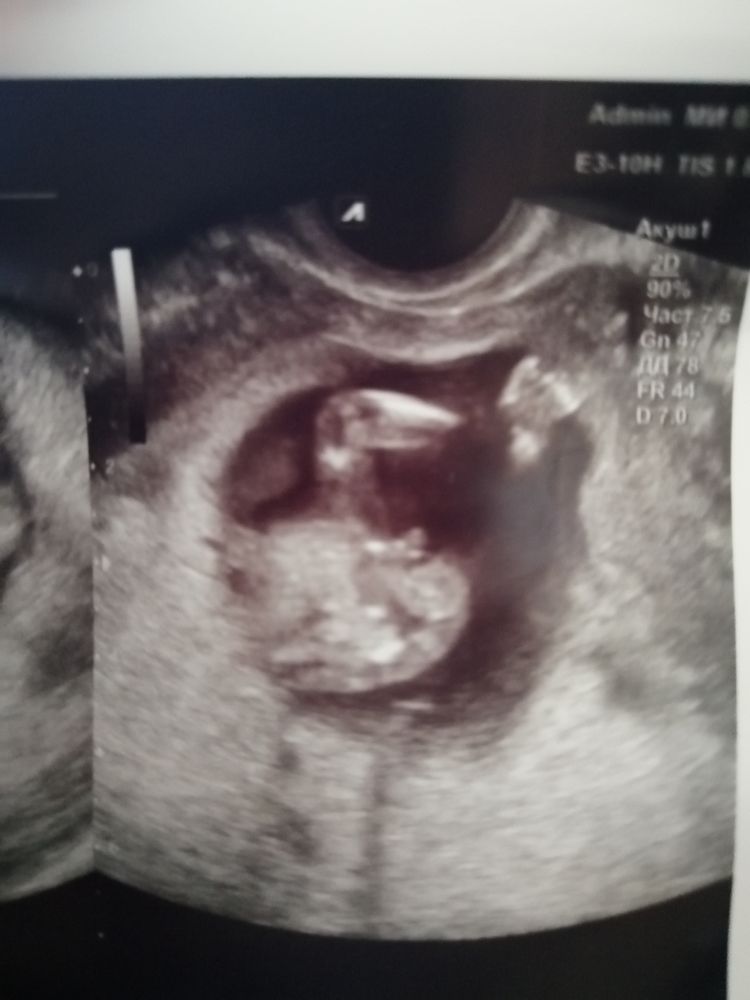

Ирина в Благополучная беременность 3 года Мальчик😊? УЗИ, КТГ, доплер Девочки, это уже точно мальчик? 14-15 недель Посмотрите еще 20 записей на эту тему Лучший ответ Юлия По такому ракурсу не скажешь, нужно сбоку смотреть. То, что торчит- это половой бугорок, а то, что рядом- лабиоскротальные складки. 24.08.2022 Ответить Отменить Ответить Ксения Мальчик 👦 24.08.2022 Ответить Мария Похоже на динозавра😁 24.08.2022 Ответить MoZi Мужик! 24.08.2022 Ответить Angelina 100000% пацан Во всей своей красе 😅 24.08.2022 Ответить Z.S. Да) 24.08.2022 Ответить Насть А я вообще не могу понять что там🤦😔как понять что есть что? 24.08.2022 Ответить Аня Пацан)) 24.08.2022 Ответить Мальчик😊? Не видно эмбриона Чаты Беременных Выберите чат: Январята-2026 Февралята-2026 Мартята-2026 Апрелята-2026 Майчата-2026 Июнята-2026 Июлята-2026 Августята-2026